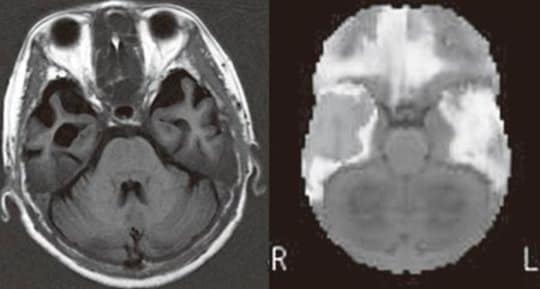

「急に言葉が分からなくなった」60代女性の脳画像

※60代女性。お金の計算もできて、買い物に行っても同じ物を買ってくることはない。夫の顔も覚えている。しかし「言葉が分からなくなった」と困っていた。頭部MRIでは両側(特に右側)の側頭葉に萎縮がみ られる。脳血流SPECT(3D-SSP)では明らかにその場所の血流が低下していた。アルツハイマー型認知症で特徴的とされる後部帯状回、楔前部の血流低下は認めない。この方は左利きなので、右側に言語機能があるようである。